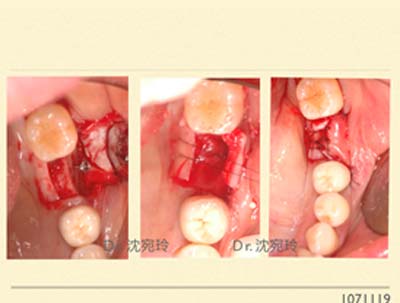

像如下的case植牙長度只能放到8 mm,再多就可能撞到神經管,這時候植體寬度就很重要,以第一大臼齒最好有5.5mm以上較安全,以迎接在咬合功能行使上的力量。那麼換算骨寬度,為加上植體的頰舌側左右需有2 mm,理想在牙脊寬度一共需9.5 mm以上,等同於現況植入後有大半是露出來的,為保守起見,我們常常先補一次骨粉和再生膜,另外在再生膜下方搭一德國帳棚釘,以維持住新骨頭生長的空間。

等6個月,我們即可把帳篷釘移除並進行植牙,屆時骨頭條件一定比現在好囉!若第一階段沒長到理想的,第二次再繼續補就好囉!

這裡隱藏最重要的事是,補進去的骨頭要能被肉『包起來』,那麼翻瓣後的『鬆弛』就很吃功夫啦!還要能做到縫合後不血呼呼,以及術後疼痛度低。若回診時,病患說『我一顆止痛藥都沒吃,不痛啊!』那就是手術醫師最欣慰的事了!!